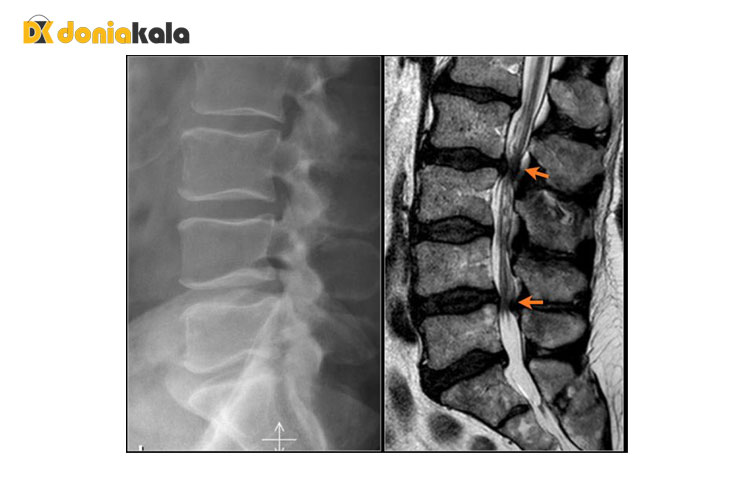

تست و تشخیص: روش های تست در زیر ذکر شده است. رایج ترین تصویربرداری برای این بیماری ام آر آیی MRI است. اشعه ایکس ساده از ناحیه آسیب دیده اغلب برای تکمیل ارزیابی مهره اضافه می شود. لطفاً توجه داشته باشید که فتق دیسک در اشعه ایکس ساده قابل مشاهده نیست. سی تی اسکن و میلوگرام بیشتر قبل از MRI استفاده می شد، اما در حال حاضر به ندرت به عنوان تصویربرداری تشخیصی اولیه سفارش داده می شود، مگر اینکه شرایط خاصی وجود داشته باشد که استفاده از آنها را تضمین کند. الکترومیوگرام به ندرت استفاده می شود.

اشعه ایکس: استفاده از تابش برای تولید فیلم یا تصویر بخشی از بدن می تواند ساختار مهره ها و طرح کلی مفاصل را نشان دهد. اشعه ایکس از ستون فقرات برای جستجوی سایر علل بالقوه درد مانند تومورها، عفونت ها، شکستگی ها و غیره گرفته می شود.

اسکن توموگرافی کامپیوتری (CT یا CAT scan): یک تصویر تشخیصی که پس از خواندن اشعه ایکس توسط کامپیوتر ایجاد می شود. می تواند شکل و اندازه کانال نخاعی، محتویات آن و ساختارهای اطراف آن را نشان دهد.

تصویربرداری رزونانس مغناطیسی ام آر آیی (MRI) : یک آزمایش تشخیصی که تصاویر سه بعدی از ساختارهای بدن را با استفاده از آهنرباهای قدرتمند و فناوری رایانه تولید می کند. می تواند طناب نخاعی، ریشه های عصبی و نواحی اطراف و همچنین بزرگ شدن، انحطاط و تومورها را نشان دهد.